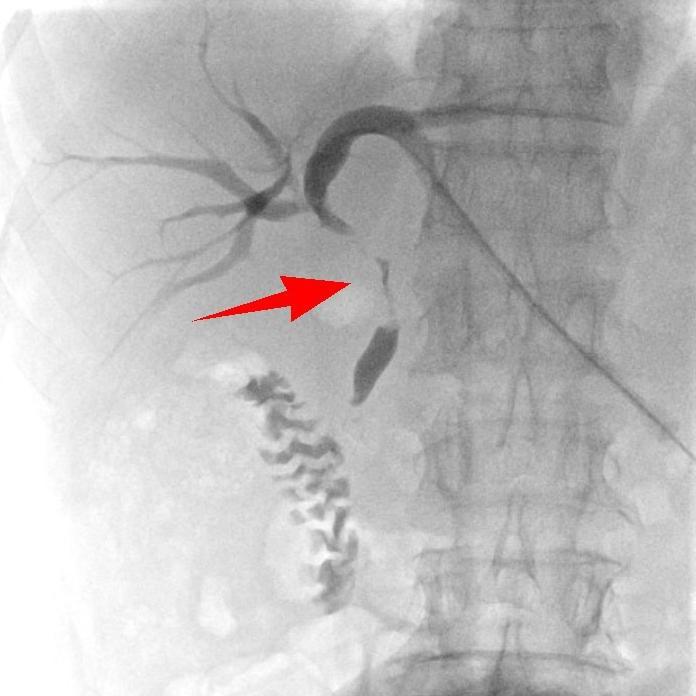

术前

“肚子不胀了,吃饭也香了!”术后第一天,杨大爷就感受到了变化。复查数据更是直观,术后第六天,各项指标基本恢复正常,黄疸彻底消退,老人面色红润如昔。如今,杨大爷已能正常生活,这场“高科技”手术的成功,不仅为他续上生命长度,更让基层患者在家门口就能享受到尖端医疗。